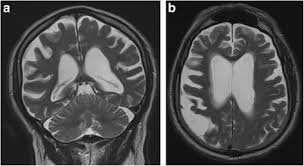

2) 뇌 영상 검사

MRI·PET 검사에서 알츠하이머는 뇌 위축, 파킨슨은 흑질 도파민 세포 감소가 확인됩니다. 영상검사는 두 질환 감별에 유용합니다.